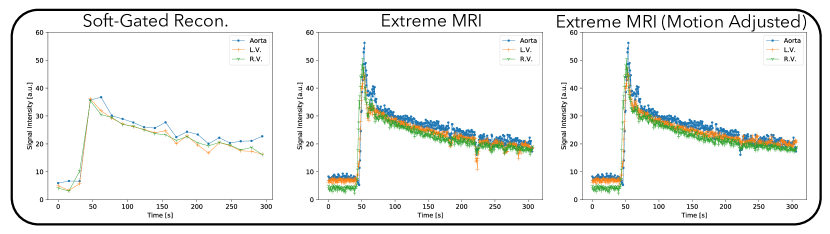

Figure 6 and Supporting Information Video S7 and S8 compare the proposed method with the soft-gated reconstruction. From Supporting Information Video S7, the proposed reconstruction shows regular respiratory motion in the beginning, but after contrast injection, breathing becomes more rapid and the patient body shifts to the right seven times. While the image quality during these bulk movements degrades, it improves as soon as the patient body returns to the original position. Similar to the first DCE dataset, distinct phases of contrast enhancement to different organs can be seen, whereas the soft-gated reconstruction merges all dynamics into one frame, including the bulk motion. From the signal intensity curves in Figure 7, the peak contrast enhancements are higher for the proposed reconstruction than for the soft-gated reconstruction. Dips in the signal intensity curves in later parts of the scan can be seen for the proposed reconstruction, which corresponds to when bulk motions occur. A motion adjusted plot was created by manually tracking the voxels over time. Variations due to bulk motions in the signal intensity plots are mostly removed after motion adjustment.

Figure 4, 6, and 8 all show that the proposed reconstruction displays much finer dynamics that are not represented in soft-gated reconstructions with low frame-rates. Distinct phases of contrast enhancements in different organs can be seen, which are more physiologically accurate. The benefits of higher temporal resolution can also be seen from signal intensity curves. In particular, signal intensity peaks of the aorta are much higher in the proposed reconstruction, but are averaged out in the soft-gated reconstruction. While bulk motion still affects the overall image quality as shown in Figure 6, the proposed reconstruction allows us to retrospectively adjust for bulk motion when computing the signal intensity curves, which can be useful for quantification purposes.